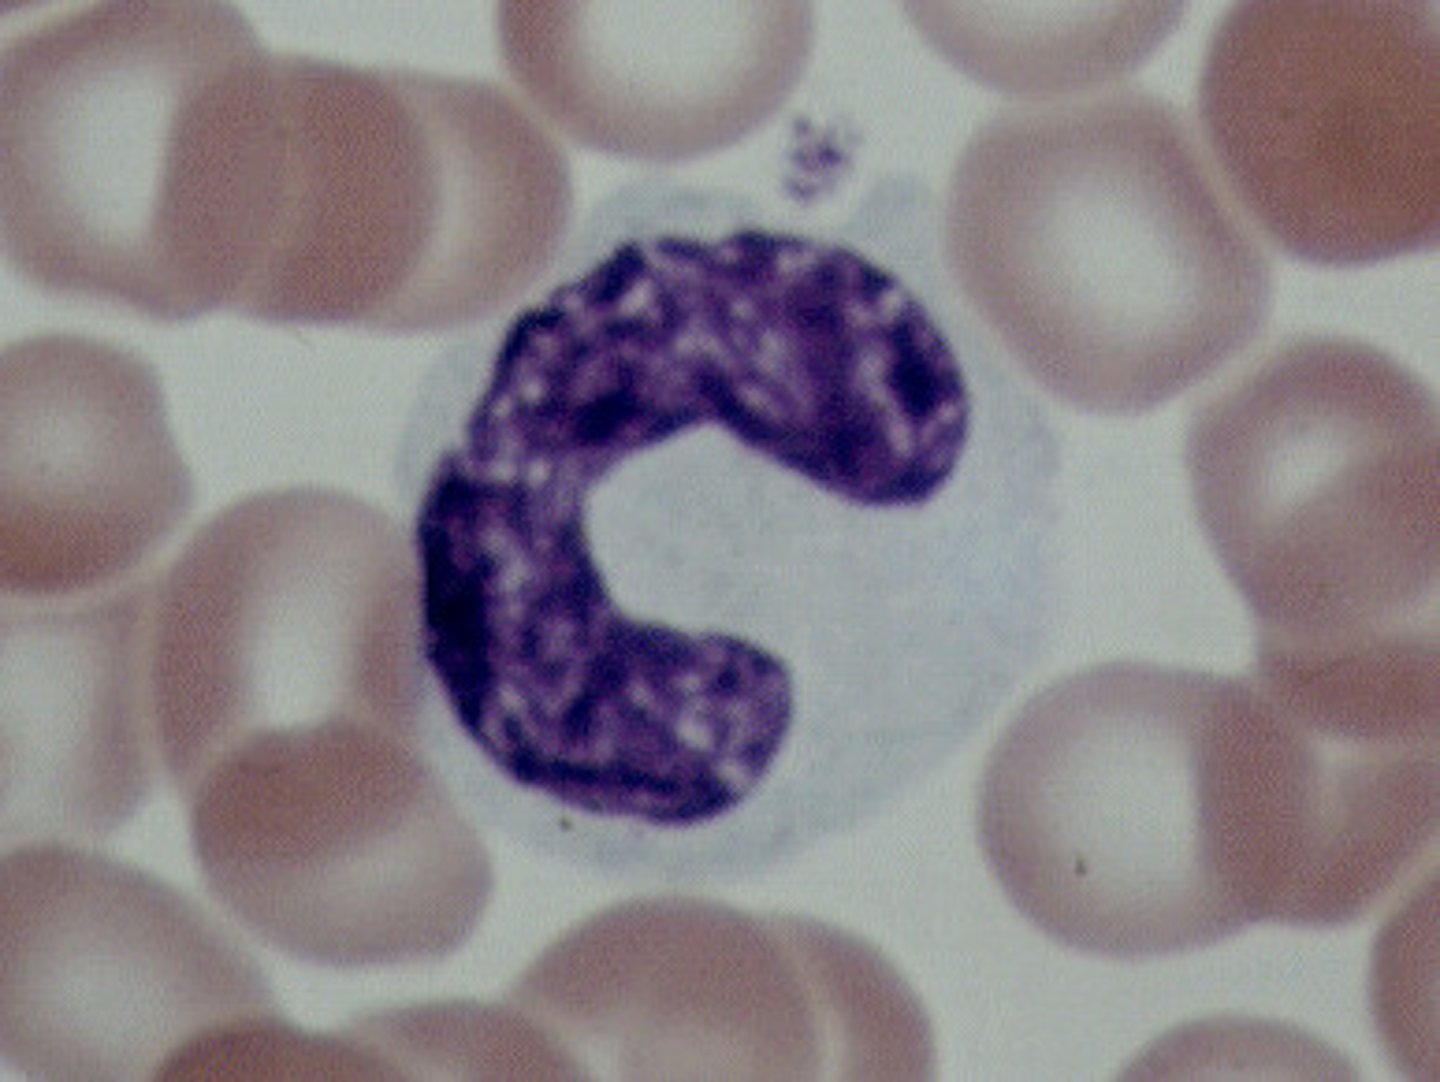

Basophils

Structure: Nuclei is U or S shaped but is obstructed by HUGE blue granules

Function: A WBC that produces histamine --> causing inflammation during an immune response

Where does the name basophils come from?

Their granules stain blue with hematoxylin dye